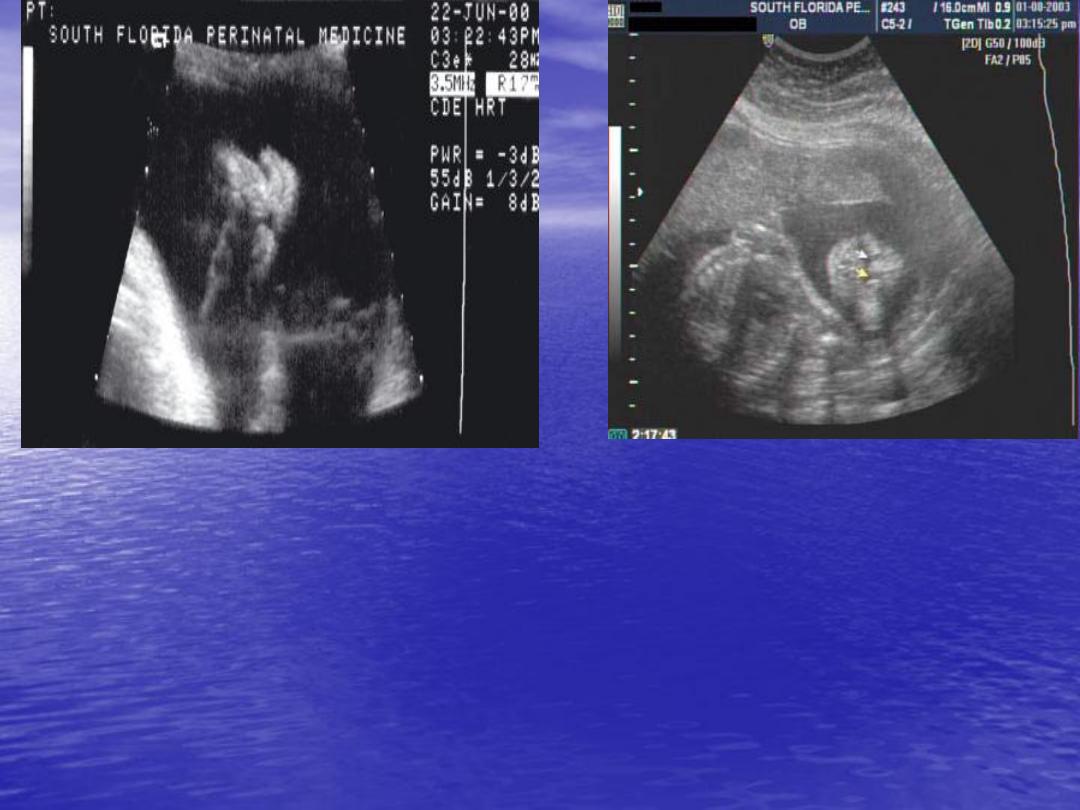

Cleft lip and palate

Cleft lip and cleft palate

are the

second

most

frequently occurring of the major congenital

anomalies they occur in

1:750-1:1000

,club foot

being the most common.